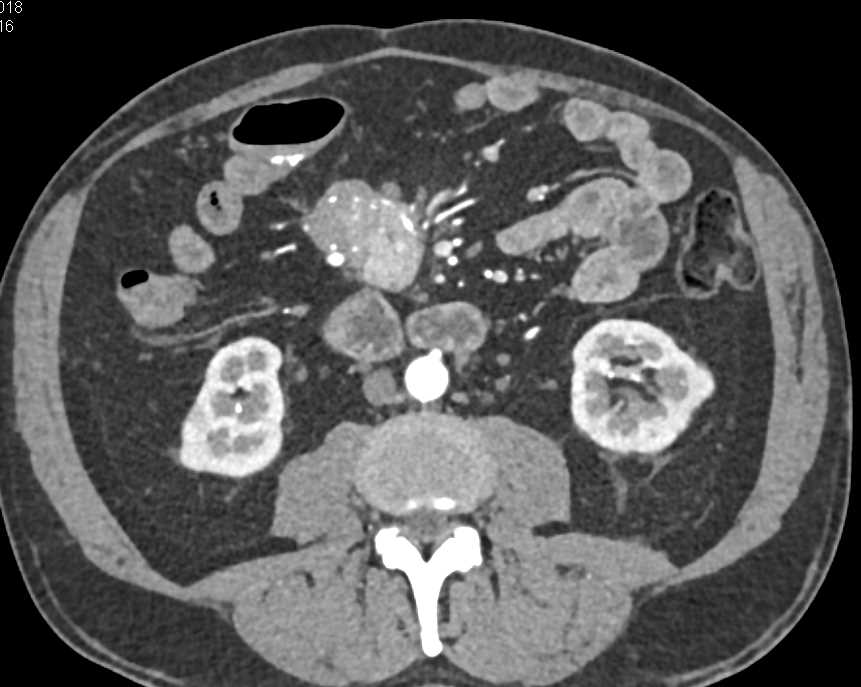

Carcinoid Tumor with Desmoplastic Reaction